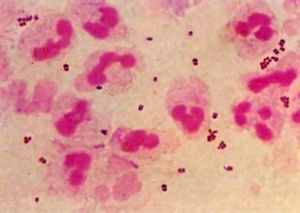

淋病奈瑟菌形態與腦膜炎球菌相似。革蘭染色陰性,圓形或卵圓形,直徑約為0.8μm。常呈雙排列,菌體相接觸面略凹陷,形似一對咖啡豆。急性淋病患者標本塗片鏡下觀察時,淋病奈瑟菌多存在於中性粒細胞內,慢性淋病時則多在細胞外。淋病奈瑟菌無鞭毛,但有菌毛,不形成芽胞,分離初期有莢膜。

淋病奈瑟菌呈卵圓或豆狀,常成雙排列,鄰近面扁平或稍凹,像兩瓣黃豆對在一起,大小0.6μm×0.8μm。革蘭氏染色陰性,呈粉紅色,美藍染色呈藍色。急性炎症期細菌多在患者分泌物的少部分中性粒細胞的胞漿中,慢性期則多在細胞外,且有些可呈單個球形或四聯狀。人工培養後形態亦常呈球形、單個、成雙或四聯排列。